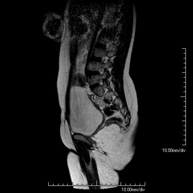

URO-RMProva diagnòstica no invasiva que consisteix en l'obtenció d'imatges d'alta definició anatòmica del sistema urinari mitjançant l'ús d'un camp electromagnètic i ones de ràdio (amb un emissor i un receptor). No utilitza radiació ionitzant. Cal contrast paramagnètic (Gadolini) que s'excreta pel sistema urinari i permet obtenir imatges en 2D i 3D.